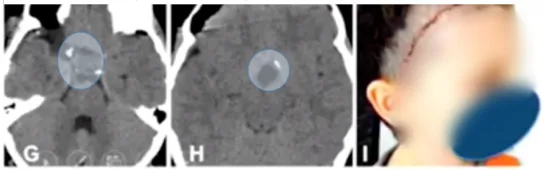

术前:视力受损

8岁的男孩,因视路-下丘脑胶质瘤引起视力受损而就诊,这个肿瘤位于他的视路和下丘脑附近,甚至扩展到了第三脑室,并延伸至梅克尔腔。

术后早期CT扫描显示肿瘤完全切除,没有出现局部血肿,患儿没有出现额外的并发症。术后两周,美容效果令人满意,面部皮肤切口恢复良好。